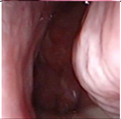

Figure 1. Sample of Nasal Endoscopy indicating Polyp (left) vs Non-Polyp (right)

[6,9] demonstrated the feasibility of a CNN-based system for the automated detection and classification of nasal polyps and inverted papillomas from nasal endoscopic images. The use of endoscopic imaging, akin to colonoscopy in colorectal polyp detection, underscores the adaptability of AI-based diagnostic tools to different medical imaging modalities. The ability of AI to assist clinicians in differentiating between various nasal cavity mass lesions, a task demanding considerable expertise, is particularly promising.